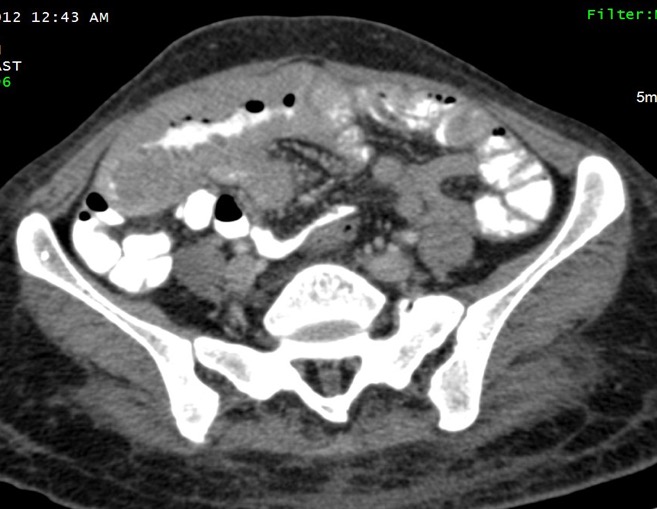

2. GIT

- Bulky, fungating masses

- Focal/circumferential wall thickening

- With/without excavated masses

- Associated with extensive lymphadenopathy